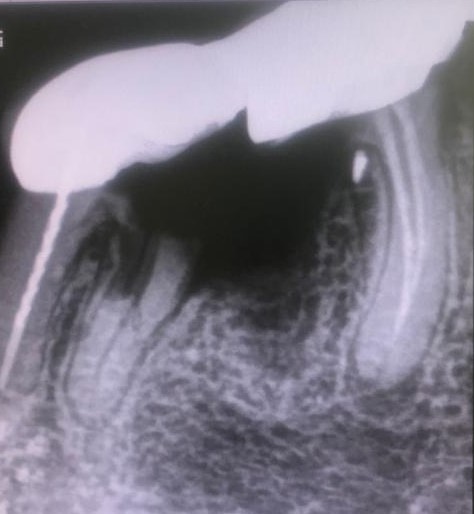

Presentamos un nuevo caso en el que la paciente presenta un gran dolor en su prótesis antigua (15 años) sobre dientes naturales tallados en zona inferior de molares. Es una paciente muy bruxómana, se unieron dos molares tallados con dos coronas. En el caso que presentamos el molar anterior estaba endodonciado ya antes de colocar la prótesis fija, pero el molar distal no. Y éste era la causa del gran dolor. Esto es por haberse filtrado creando caries y destrucción dentaria que llegaba al nervio. En conclusión, produciendo una gran pulpitis.

Esto provocaba en la paciente un gran dolor, pero ella no contemplaba en ese momento la opción de levantar la prótesis para explorar las piezas que había debajo, poder visualizar la destrucción dental y rehacer todo con una prótesis nueva. Por tanto, para quitar el dolor normalmente habría que haber hecho las extracciones de los dos molares, lo cual sería muy invalidante. En la clínica decidimos hacer una endodoncia de la raíz distal del último molar a través de la prótesis por la zona oclusal, y hacer odontosecciones de las raíces lesionadas sin quitar la prótesis. Ésta va permanecer tal como estaba.

La técnica quirúrgica para este menester es parecida a una apicectomía, pero en lugar de quitar solo el ápice radicular quitamos toda la raíz dental. Así pues lo que se hizo fue extracción de la raíz distal del primer molar y extracción de la raíz mesial del segundo molar. Con lo que la prótesis sigue teniendo dos pilares.

En conclusión, lo que hicimos fue alisar la prótesis por debajo de forma que quede higiénica y por tanto no retenga restos. La técnica quirúrgica quedo muy bien. El tiempo de inflamación de la cara es como si se hubiera hecho la extracción de la muela del juicio, pero una vez se va la inflamación el paciente sigue haciendo vida normal, como el día que se le puso la prótesis.

Lo más importante, es que a los diez días se quitan los puntos y poco a poco se vuelve a la normalidad.

Con la secuencia de imágenes se comprende muy bien la técnica quirúrgica realizada.